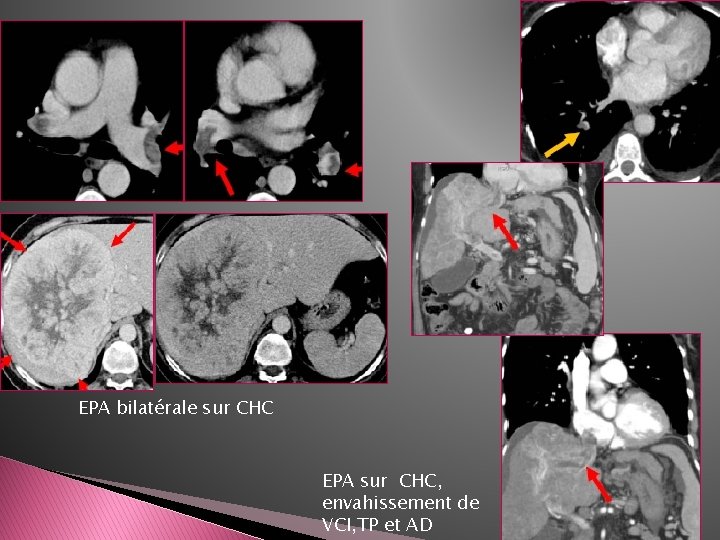

� Emboles tumoraux: -Le plus svt embolie périphérique sous segmentaire -Plus rarement EPA proximale (envahissement cave inférieur de CHC, d’ADK rénal ou de chorio carcinome) -Rehaussé par le PDC

EPA tumorale sur tumeur de Grawitz bilatérale/ envahissement cave inférieur EPA sur tumeur de Grawitz droite/ envahissement cave inférieur

EPA bilatérale sur CHC EPA sur CHC, envahissement de VCI, TP et AD